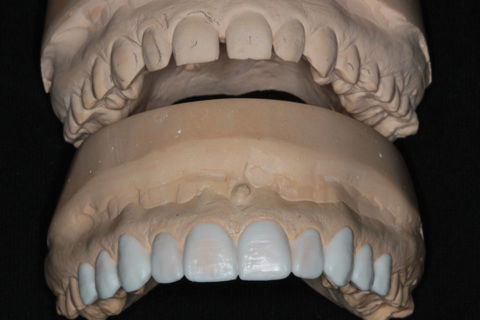

Enceramento Diagnóstico referenciado pelo DSD

1º Passo: Planejamento Digital Smile Design – DSD + Enceramento Diagnóstico;